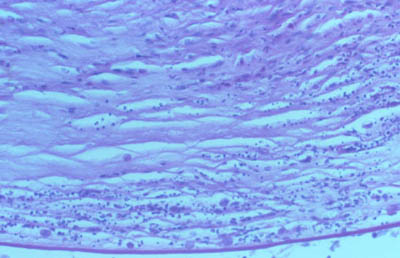

Tejido corneal Procesado

H&E

PAS

CW